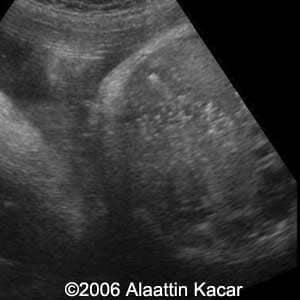

Gallstones Alaattin Kacar, MD Sureyya Paksoy MD Burhan Seker, MD Ender Birgul, MD Article Published: Jun 8, 2006 Balikesis, Turkey These are several images of a fetus with multiple gallstones Discussion Board Start a discussion about this article Add to Favorites Favorite